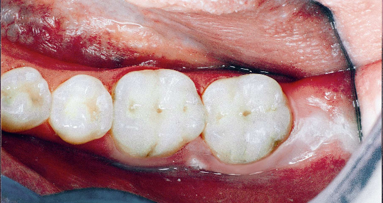

IOWA CITY, USA: I ricercatori della Università dell'Iowa hanno sviluppato un rivoluzionario BIOPATCH che potrebbe aiutare la riparazione ossea nelle sezioni mancanti o danneggiati, con applicazioni in molti rami della medicina.

Tipicamente, il contributo della proteina che stimola la crescita, basata su iniezioni ripetute nell'osso, è costosa e invasiva. I risultati della ricerca suggeriscono che il sistema di rilascio sulle matrici attivate con PDGF-B rilasciano tali proteine localmente, per un periodo prolungato. Secondo i ricercatori, ciò porta ad un grande potenziale per l'applicazione clinica.